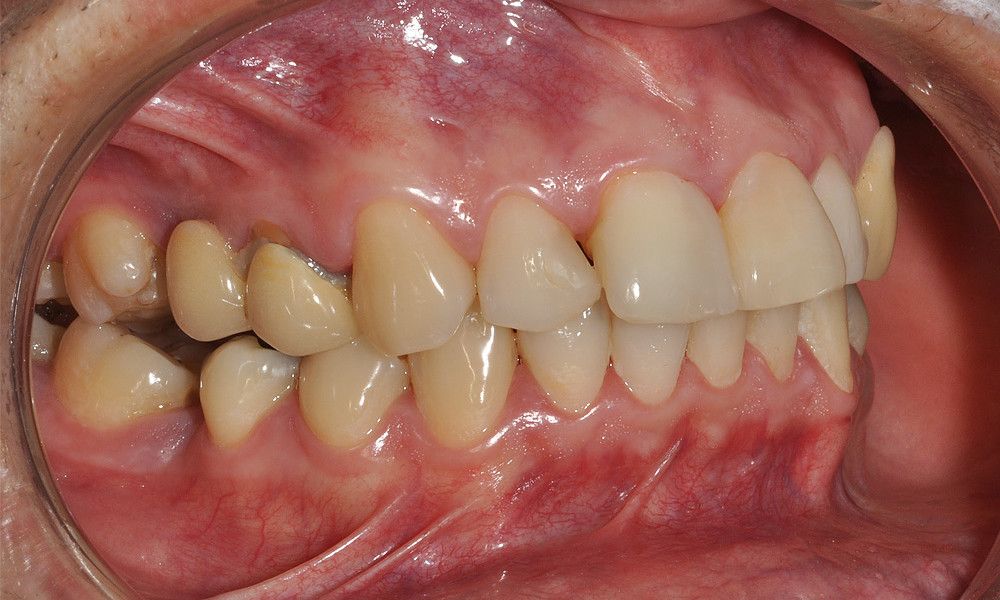

Reporte del Caso: Paciente sexo masculino, 36 años, con diagnóstico de esquizofrenia y trastorno bipolar en tratamiento. Consulta por el recambio de dos prótesis fijas plurales (PFP) de reemplazo de dientes 4 y 13 con pilares en piezas 3, 5, 12 y 14 mediante rehabilitaciones unitarias de los dientes pilares y reemplazo mediante implantes en zonas edéntulas.

El estudio imagenológico evidencia una pérdida ósea severa en altitud y grosor, situación que complejiza la colocación de un implante. Se analizan alternativas de tratamiento y se opta por una vestibuloplastía mediante autoinjerto conectivo de mucosa palatina que se reposiciona sobre la zona del defecto óseo. Además se realiza retratamiento de ambas PFP, ahora en zirconia, por motivos estéticos y oclusales. Se realizan controles posteriores para evaluar la respuesta gingival a la vestibuloplastía.